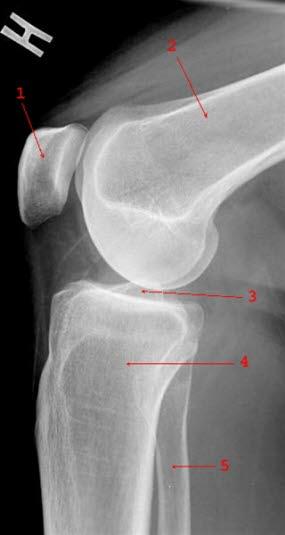

Røntgenbilde av kneleddetKneleddet utgjøres av lårbeinets og leggbeinets leddflater. Beinvevet er kledd med brusk som gjør at leddflatene glir mot hverandre med minst mulig motstand. I tillegg har kneleddet to bruskskiver (meniskene) som fremmer bevegeligheten i leddet. Artrose i kneleddet kalles det når leddbrusk eller bein i kneleddet er endret slik at overflatene ikke lenger er glatte og symmetriske. Dette kaltes tidligere slitasjegikt.

Røntgen av kneet viser typiske artroseforandringer (lette, moderate, uttalte artroseforandringer) og bekrefter diagnosen. Røntgenbildene forteller likevel ikke hele sannheten, fordi det kan være manglende samsvar mellom graden av plager og graden av forandringer på røntgen.